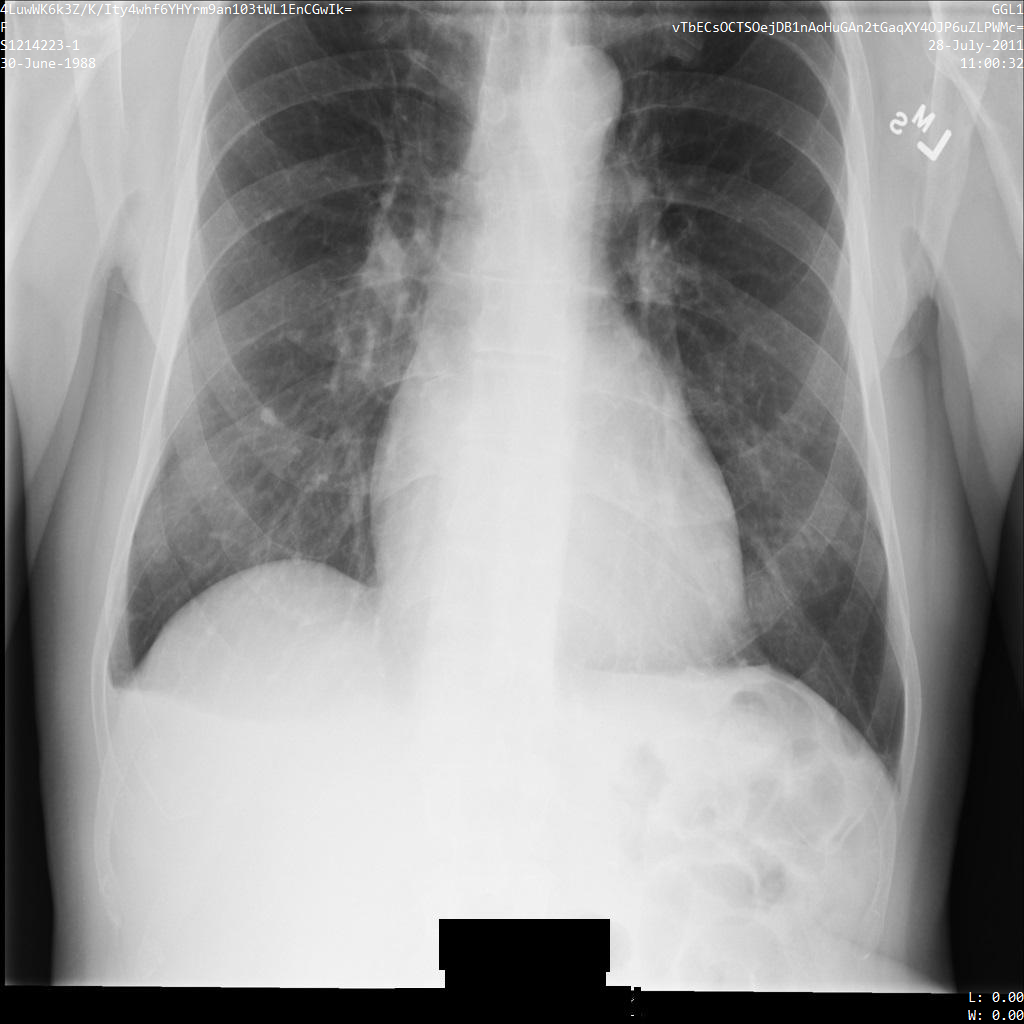

Une fois l'image envoyée à l'API Cloud Healthcare à l'aide des options REDACT_ALL_TEXT et DEIDENTIFY_TAG_CONTENTS, elle apparaît comme suit. Observez les modifications suivantes :

- Les noms situés en haut à gauche et en haut à droite de l'image ont été transformés à l'aide d'un élément

CryptoHashConfig. - Les dates situées en haut à gauche et en haut à droite de l'image ont été transformées à l'aide d'un élément

DateShiftConfig. - Le texte incrusté dans le bas de l'image est masqué

Une fois l'image envoyée à l'API Cloud Healthcare à l'aide du profil DEIDENTIFY_TAG_CONTENTS, elle apparaît comme suit :

Observez les modifications suivantes :

- Les noms situés en haut à gauche et en haut à droite de l'image ont été transformés à l'aide d'un élément

CryptoHashConfig. - Les dates situées en haut à gauche et en haut à droite de l'image ont été transformées à l'aide d'un élément

DateShiftConfig.